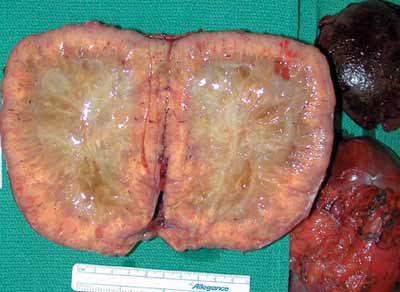

Autosomal dominant polycystic kidney disease (ADPKD) is common. Presenting symtpoms include hypertension, hematuria, proteinuria, and renal insufficiency.